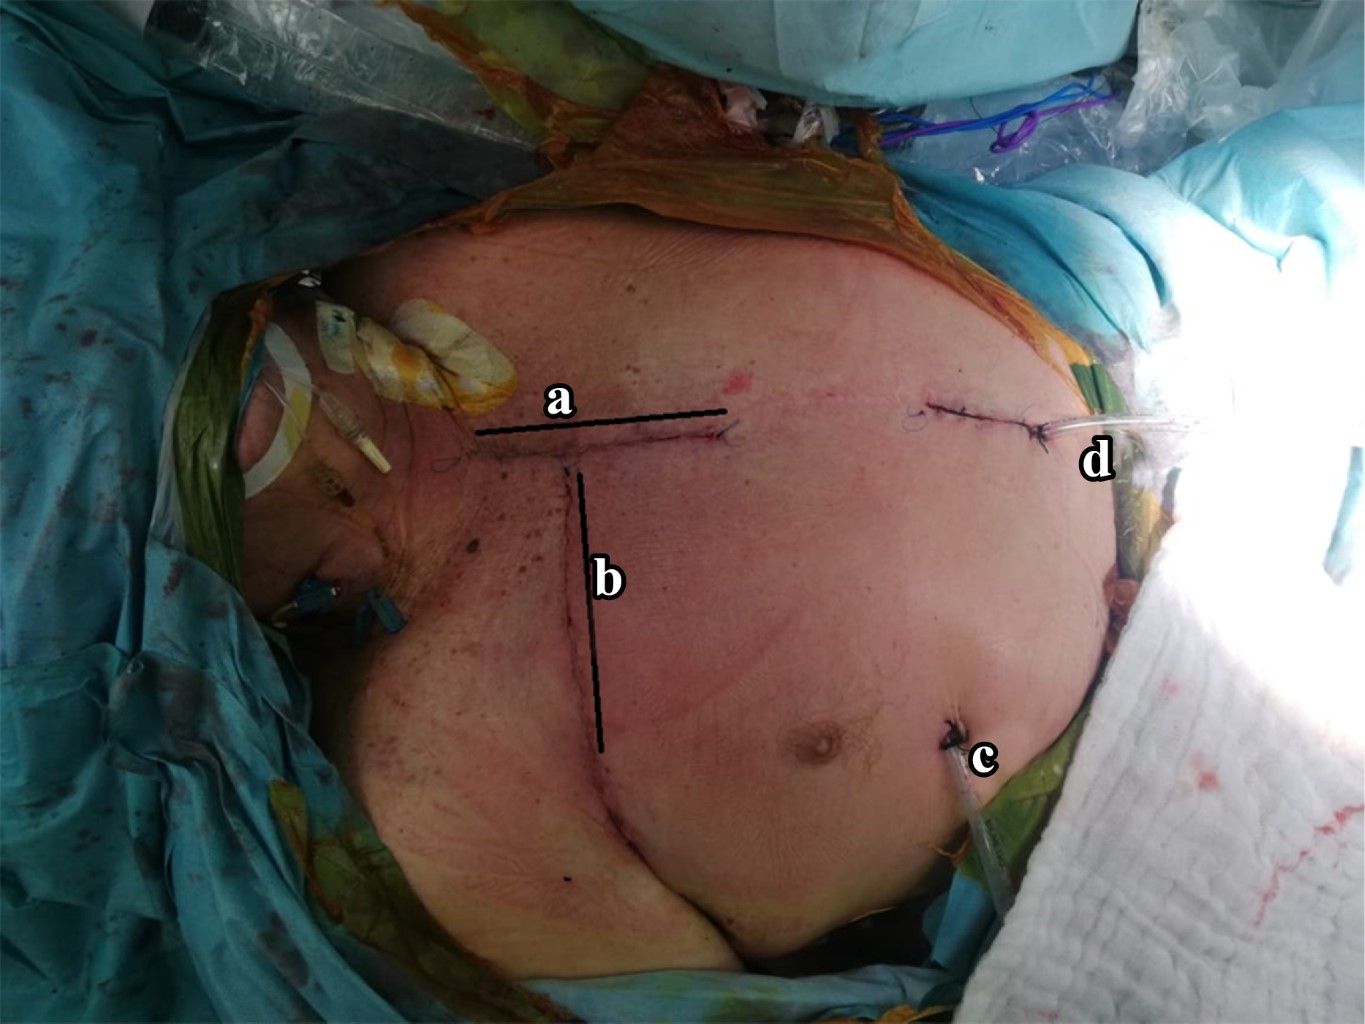

Paciente con espondilodiscitis que presentó deformidad cifótica con compromiso neurológico a nivel torácico superior, quien fue tratado con un nuevo abordaje torácico anterior infraclavicular derecho, como nueva técnica quirúrgica alternativa. Varón de 72 años con deformidad en cifosis secundaria a espondilodiscitis T2-T3 ASIA "C", tratado con instrumentación cervicotorácica posterior C5 a T6 y abordaje anterior transtorácico infraclavicular derecho con colocación de cilindro expandible. Dentro de la revisión bibliográfica realizada en los buscadores no se encontraron técnicas similares a la descrita en este artículo. Dada la complejidad del abordaje quirúrgico, esta nueva técnica se describe como una nueva forma de acceder a la columna torácica superior, demostrando que el abordaje torácico anterior infraclavicular derecho es una nueva alternativa para acceder a la columna torácica superior desde T1 a T4.

Figura 3